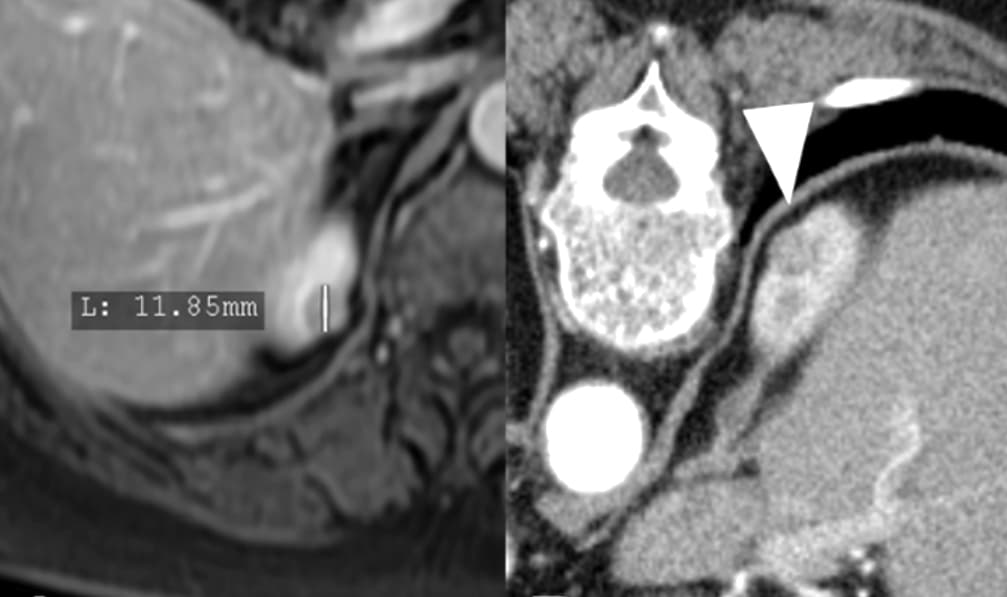

Traitement percutané des tumeurs rénales : les recommandations diffèrent en Europe et aux USA

Les techniques percutanées d’ablation percutanée, thermique ou radiothérapeutique, de tumeurs rénales gagnent du terrain mais les recommandations varient selon les régions. Un article publié dans la Revue European Radiology fait une synthèse des recommandations à travers le monde. Et celles-ci ne so...